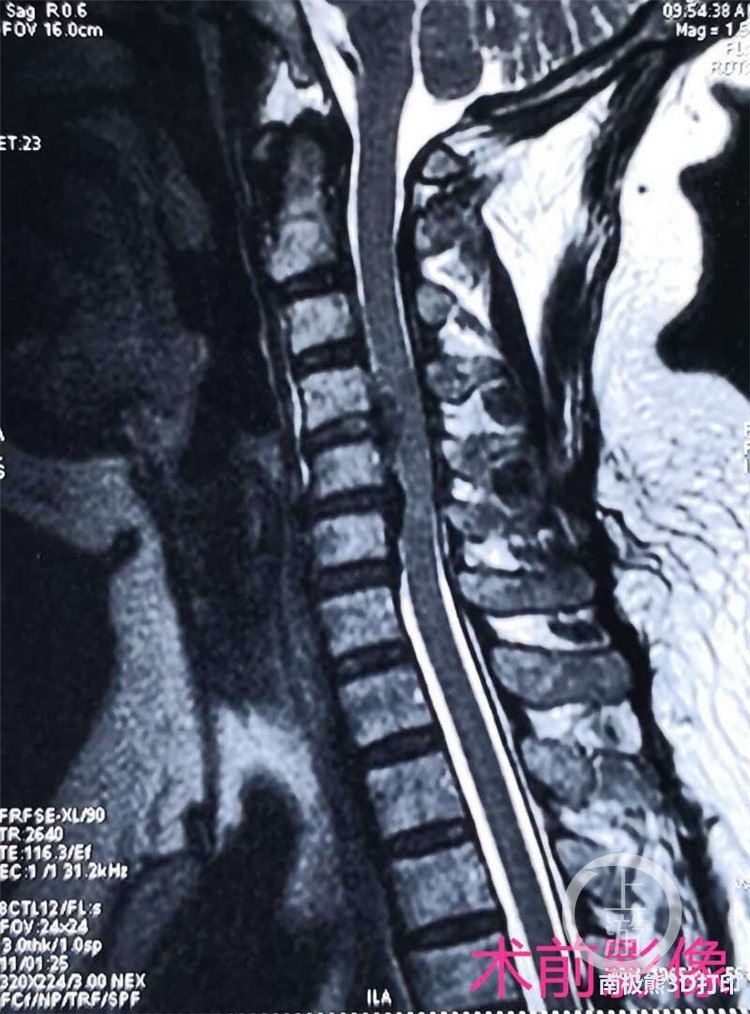

59岁的患者徐女士因四肢麻木、行走不稳1月余,来到大坪医院骨科中心就诊。经检查,确诊为C4-5及C5-6椎间盘巨大突出导致颈脊髓严重受压,同时合并发育性颈椎管狭窄、后纵韧带骨化,若不及时治疗,将严重影响患者生活质量。

因突出物巨大,担心经椎间隙减压不够彻底,决定行C5椎体次全切除、植骨融合术。以前采用的植骨材料钛网、同种异体骨环均可能出现不同程度假体沉降、椎间高度丧失等风险。

充分征求患者意见后,骨科中心手术团队经讨论决定,为患者选用国内原研、具有完全自主知识产权的3D打印人工椎体替代原有植骨材料。此材料完全按照仿生学原理,具有经过力学优化的特殊结构,比传统技术制造的钛网具有更强的承重力,能克服钛网存在的缺点,与手术处上下椎骨完美嵌合。

术前,该科依据患者最新的CT和MRI的影像学数据资料,通过医工结合和反复论证,按照1:1的3D打印复制模型,制造出一个长度2厘米、直径1.4厘米大小的立体精确全颈椎假体。术中,在麻醉科配合下,刘鹏主任团队在显微镜辅助下实施手术,成功完成3D打印人工颈椎椎体植入手术。术后次日,患者即可下地,症状完全消失。 据刘鹏主任介绍,3D打印是骨科领域近年来快速发展的领域之一,该院骨科中心一直注重探索和尝试骨科智能化诊疗手段,为广大患者解除病痛谋福。该人工椎体是由钛合金粉末通过3D打印技术制造完成,具有良好的生物相容性。同时,3D打印的骨小梁结构,拥有类松质骨的弹性模量,避免了应力遮挡和骨吸收,还可以诱导骨细胞进行迁移和增殖,具有可靠的骨整合性。椎体与上下相邻节段终板之间是面与面的接触,可以有效地避免椎体终板塌陷和椎间高度丢失等问题,医学前景及临床意义极大。